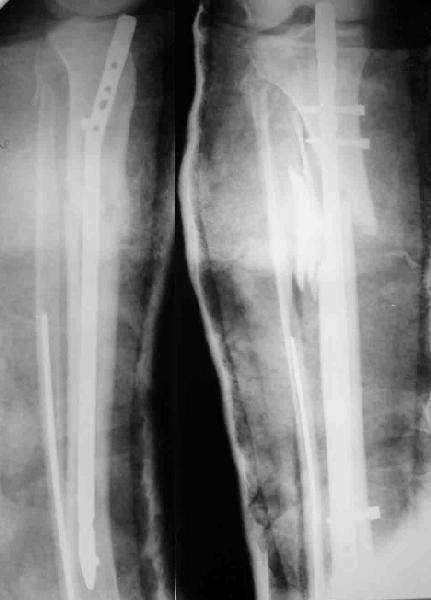

Декабрь 2003

22 июня 2004

Еще раз спасибо! Сделали вчера. Все прошло по плану, интраоперационное фото после удаления пластинки и итоговые снимки прилагаю. Гвоздь бесканальный 12 мм. Сегодня пациентка уже ходит по палате с одним костылем.